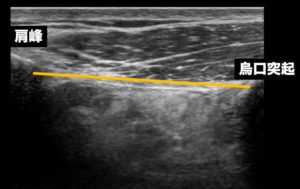

CALは烏口突起から肩峰に向かって走行しますが

ここではこの鳥口肩峰靭帯の位置と、プローブの置く場所を確認し

実際の画像を見てみましょう↓

エコー画像